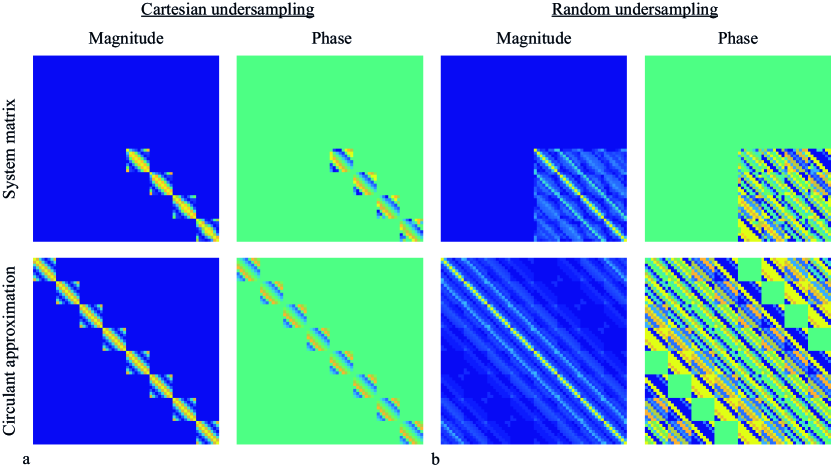

The fully built system matrix is compared with its circulant approximation in Fig. 4a for Cartesian undersampling and a system matrix size of . Both the magnitude and phase parts of contain many zeros due to the lack of coil sensitivity in a large part of the image domain when using the posterior coil. These zeros are not present in the circulant approximation, since the circulant property is enforced by neglecting all off-diagonal elements in . The introduced entries in the circulant approximation do not add relevant information to the system, because the image vector on which the system matrix acts contains zero signal in the region corresponding with the newly introduced entries. Therefore, the magnitude and phase are approximated well by assuming the circulant property. Fig. 4b shows the same results for random undersampling, demonstrating the generalisability of this approach to different sampling schemes.